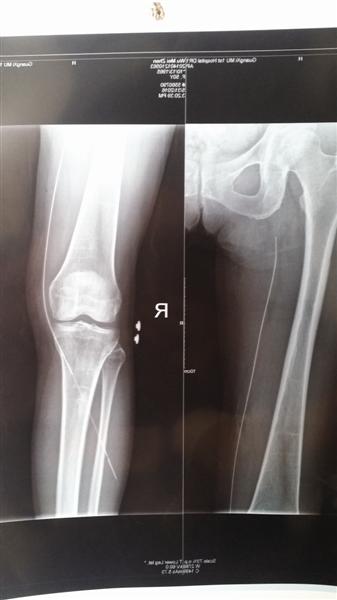

X光片显示,有长约30厘米的导丝留在吴女士右腿血管内。

一场看似普通的取异物手术,为何会被如此重视呢?原来,这个看似普通的异物可不简单,X光片显示:藏在吴女士大腿的金属质导丝,大半截滞留在血管里面,长达30多厘米。一不小心,手术发生风险的概率极高。